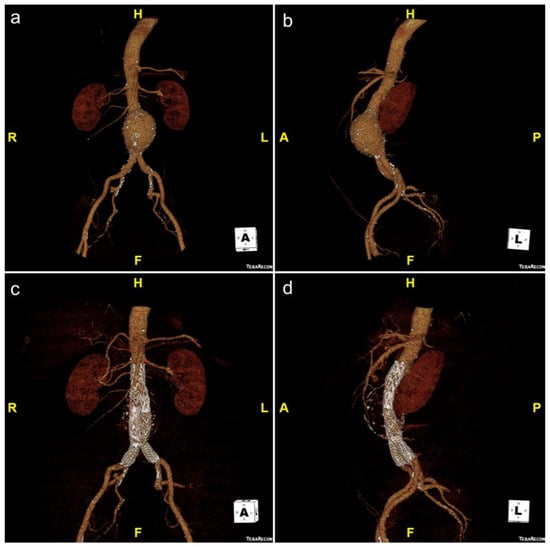

3.2. Fenestrated/Branched EVAR (FEVAR/BEVAR)